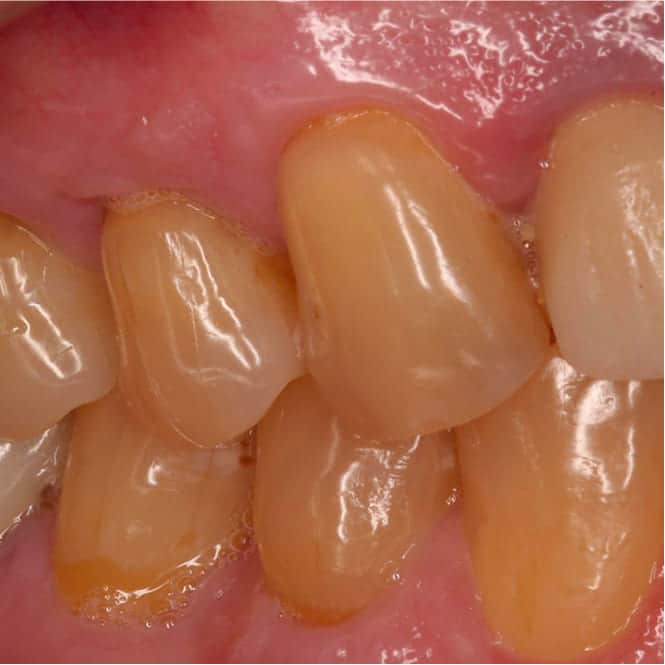

After treatment showing complete root coverage with healthy, thick gingival tissue After

At four weeks, tissue color, thickness, and margin position were all tracking well. By eight weeks, the graft had fully integrated and the tissue was mature, stable, and noticeably thicker than what had been there before.

Complete root coverage was achieved on all treated teeth. The sensitivity that had been a daily problem for Niko was gone.

The new tissue was significantly thicker than the original fragile biotype, providing a more resilient barrier against future recession. Gingival margins were at anatomically correct levels with a natural scalloped contour.

Niko reported that both his comfort and his confidence returned. He was eating normally again, no longer guarding the affected side, and no longer self-conscious about the appearance of his gums.